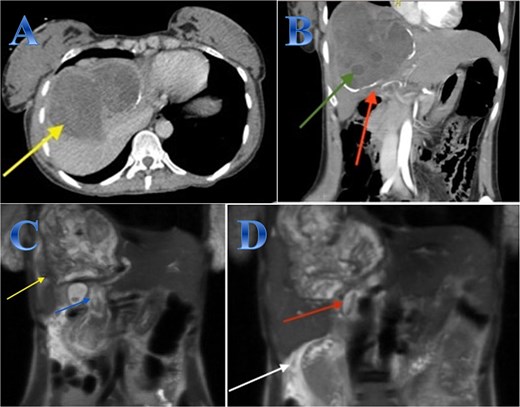

A 42-year-old woman experiences 3 weeks of right upper quadrant pain. On examination showed mild epigastric enlargement and tenderness. Laboratory tests showed eosinophilia, increases in total and direct bilirubin levels. The US discovered a large heterogenous mass with minimal expansion of IHBRs. Abdominal CT revealed large calcified right hepatic lobe cyst with dilated IHBRs (Fig. 1).

Case 1. (A & B) Sagittal and coronal CT cuts of the abdomen at venous phase showing a large peripherally calcified heterogeneous hypodense mass in the right hepatic lobe (photo A), with internal septations and small cysts (daughter cysts), with dilated IHBRs (photo B). (C & D) Coronal MRI images of the abdomen (follow up study) showing biliary extension of the lesion, CBD and the hepatic duct and sub hepatic fluid signal.

A preoperative Albendazole of 400 mg twice daily was started for 8 weeks. An ERCP paired with sphincterotomy, and stenting of the biliary ducts revealed a gelatinous substance with many daughter cysts that came through the ampulla of Vater. The severity of the lesions required an open surgical approach as it is a sizeable CE communicating with common and right hepatic ducts, treated by total peri-cystectomy and closure of the communication with common hepatic duct (CHD) and right hepatic duct (RHD). The cyst was isolated using gauze pads soaked in hypertonic saline. The cyst was punctured with a needle, and its contents were aspirated to reduce intra-cystic pressure. The gall bladder was adherent to the cyst, so cholecystectomy was done; after that, through the cystic duct, contrast material was injected, and it came through two intraparenchymal openings. These two intra-parenchymal openings were closed through deep sutures in two layers. A cholangiogram was done to make sure there was no stenosis or leakage (Fig. 1).